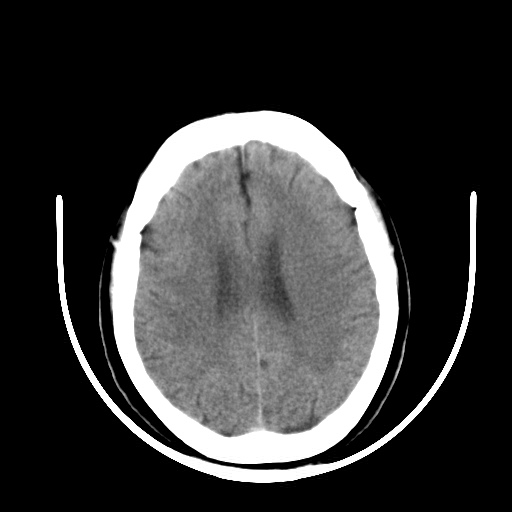

标题: CT16579:女 65岁间断性抽搐. [打印本页]

标题: CT16579:女 65岁间断性抽搐.

考虑右侧颞叶脑软化灶并脑穿通畸形;建议必要时行进一步检查。

右颞叶脑软化灶。余未见明显异常。

考虑右颞叶脑软化灶

老年脑改变